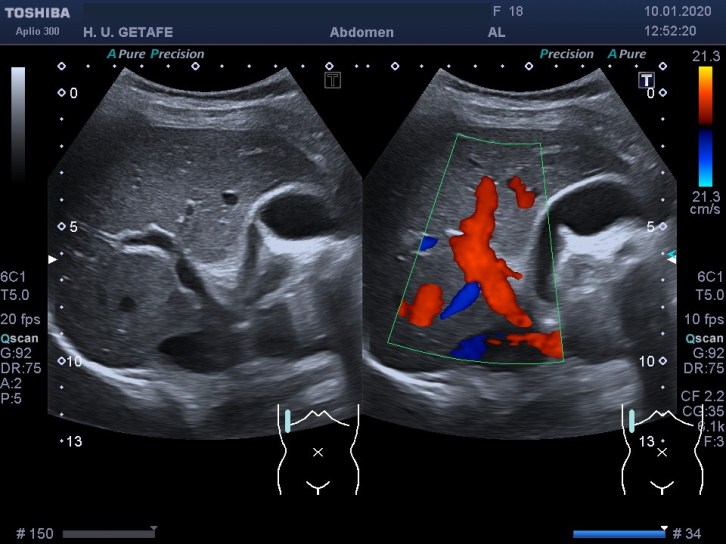

311. Doppler color y Modo Angio, dos secretos que igual no sabías.

Cuando realizamos una exploración ecográfica, el protocolo que sea, no es raro que uno de los comandos que más usemos sea el Doppler, sabemos cómo funciona el Doppler, Alejandro lo ha explicado en este blog y el libro Eco Fácil de Marbán, pero yo quiero contarte dos secretos, que seguro que sabes, pero que quiero contarlo por si hay alguien un poquito más rezagado que aún no se ha enterado.

Quiero que te preguntes si sabrías diferenciar entre una imagen Doppler Color y una imagen en Modo Angio o Doppler Power. Vas a decir que sí, que lo sabes. Y es cierto, en la mayoría de las ocasiones distinguimos estas dos técnicas por el color, una rojo y azul, otra azul o morado, u otras coloraciones según la casa comercial.

Modo Doppler Color

Modo Angio o Doppler Power

Ahora quiero que te preguntes si sabrías decirte que magnitud de la onda ultrasonográfica toma de referencia cada una de los dos comando cuando los activamos para darnos la imagen que estamos buscando…igual aquí tienes alguna dificultad, igual aquí, te he pillado¿Te sonríes?…me encanta…ah que ya lo sabes…bueno, pues lo voy a explicar para quien no lo sepa.

En la onda ultrosonográfica hay dos magnitudes claves, la longitud de onda, que es la distancia entre dos puntos de una misma onda, por ejemplo, entre sus valles o entre sus crestas, que será menor cuanto más alta sea la frecuencia, y la amplitud de la onda que es la máxima distancia que alcanza la onda, o de otro modo, lo enérgica que es esa onda.

Muy bien, en el Doppler Color (CDI) la magnitud de referencia que tomará nuestro equipo para hacer la medición de aquello que estemos interesados en estudiar será la longitud de onda. Sin embargo, en el Doppler Power o Modo Angio (Power) el equipo lee la Amplitud de la onda ultrasonográfica, la imagen de abajo.

Otra de las diferencias entre estos modos de trabajo si lo quieres llamar así es la medición de los hematíes. Me explico, cuando estamos haciendo Doppler lo que medimos es el movimiento hístico. No estamos midiendo las características ecográficas del tejido, es decir, no queremos saber si es anecoico, hipo o hiperecogénico, estamos midiendo su movimiento, el de los vasos, o el de las estructuras que puedan estar vascularizadas.

Por tanto este modo de trabajo valoriza el movimientos de los hematíes, su velocidad, y la densidad de estas células sanguíneas las mide el modo angio, por eso el Doppler color se usa para flujos rápidos (medidad cuantitativa) y el modo angio para flujos lentos (medida cualitativa), por eso el modo angio es mas sensible, así que si eres muy sensible, eres modo angio… ¿lo entiendes?